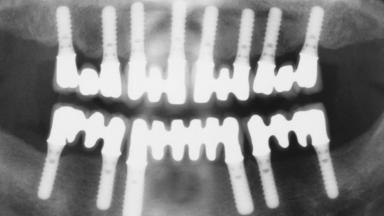

Immediate Loading of Eight Implants in the Maxilla and Six Implants in the Mandible and Final Restoration with Three-Unit and Four-Unit FDPs

Extensive scientific evidence has confirmed that immediately loaded implants with fixed full-arch provisional restorations can osseointegrate with success rates similar to conventionally or delayed loaded implants. A number of immediate-provisionalization techniques for edentulous jaws have been described. Some protocols differ when it comes to prefabricated provisional templates versus complete denture conversion; intrasurgical impressions versus direct relining; and cemented versus screw-retained provisional restorations. In this context, complete-denture conversion has been proposed for either intrasurgical impressions or direct relining. Another possibility is the utilization of a prefabricated provisional to be adapted either in the mouth (by direct relining) or in the laboratory (on a working model obtained from an intrasurgical impression).

# of Implants 14

Type of Implants One-Piece